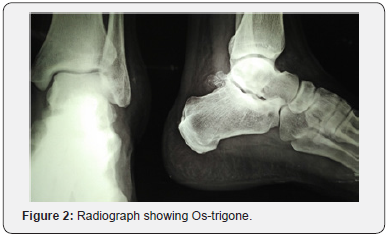

Serum calcium, uric acid, total and differential leukocyte count and ESR were within normal limits. The anteroposterior and lateral radiographs were normal except for an Ostrigone (Figure 2). An ultrasonogram was done which showed thickening of peroneal tendons with synovial hyperplasia and effusion suggesting peroneal tenosynovitis. Magnetic resonance imaging of left ankle showed few small osseous intensity structures along the posterior and lateral margins of the joint probably loose bodies. Hyper-intense signals were noted around peroneus brevis tendon and there was significant peri-tendinous fluid collection indicating peroneal tenosynovitis. Few tiny subcortical PD-FS hyper-intense foci were seen along the articular surface of tibio-talar joint indicating coexistent osteoarthritis (Figure 3). Based on the clinical findings and investigations a diagnosis of recurrent subluxation of peroneal tendons with peroneal tenosynovitis was made.